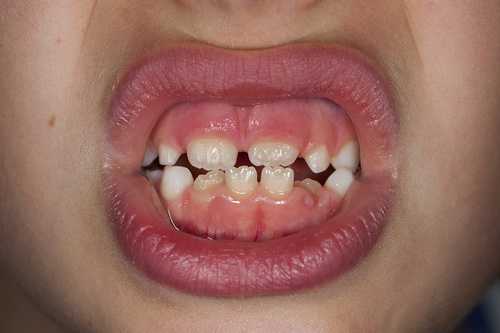

- Диастема, или щель между передними зубами. Дело даже не в заметном дефекте. Уздечка между зубами препятствует правильному положению зубов, из-за чего они травмируются и разъезжаются.

ДиастемаВозраст, подходящий для пластики